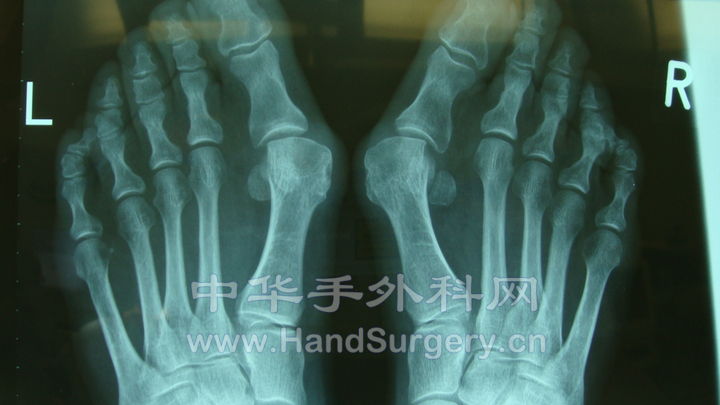

这是一个拇外翻的线片。scarf+Akin术前,术后。